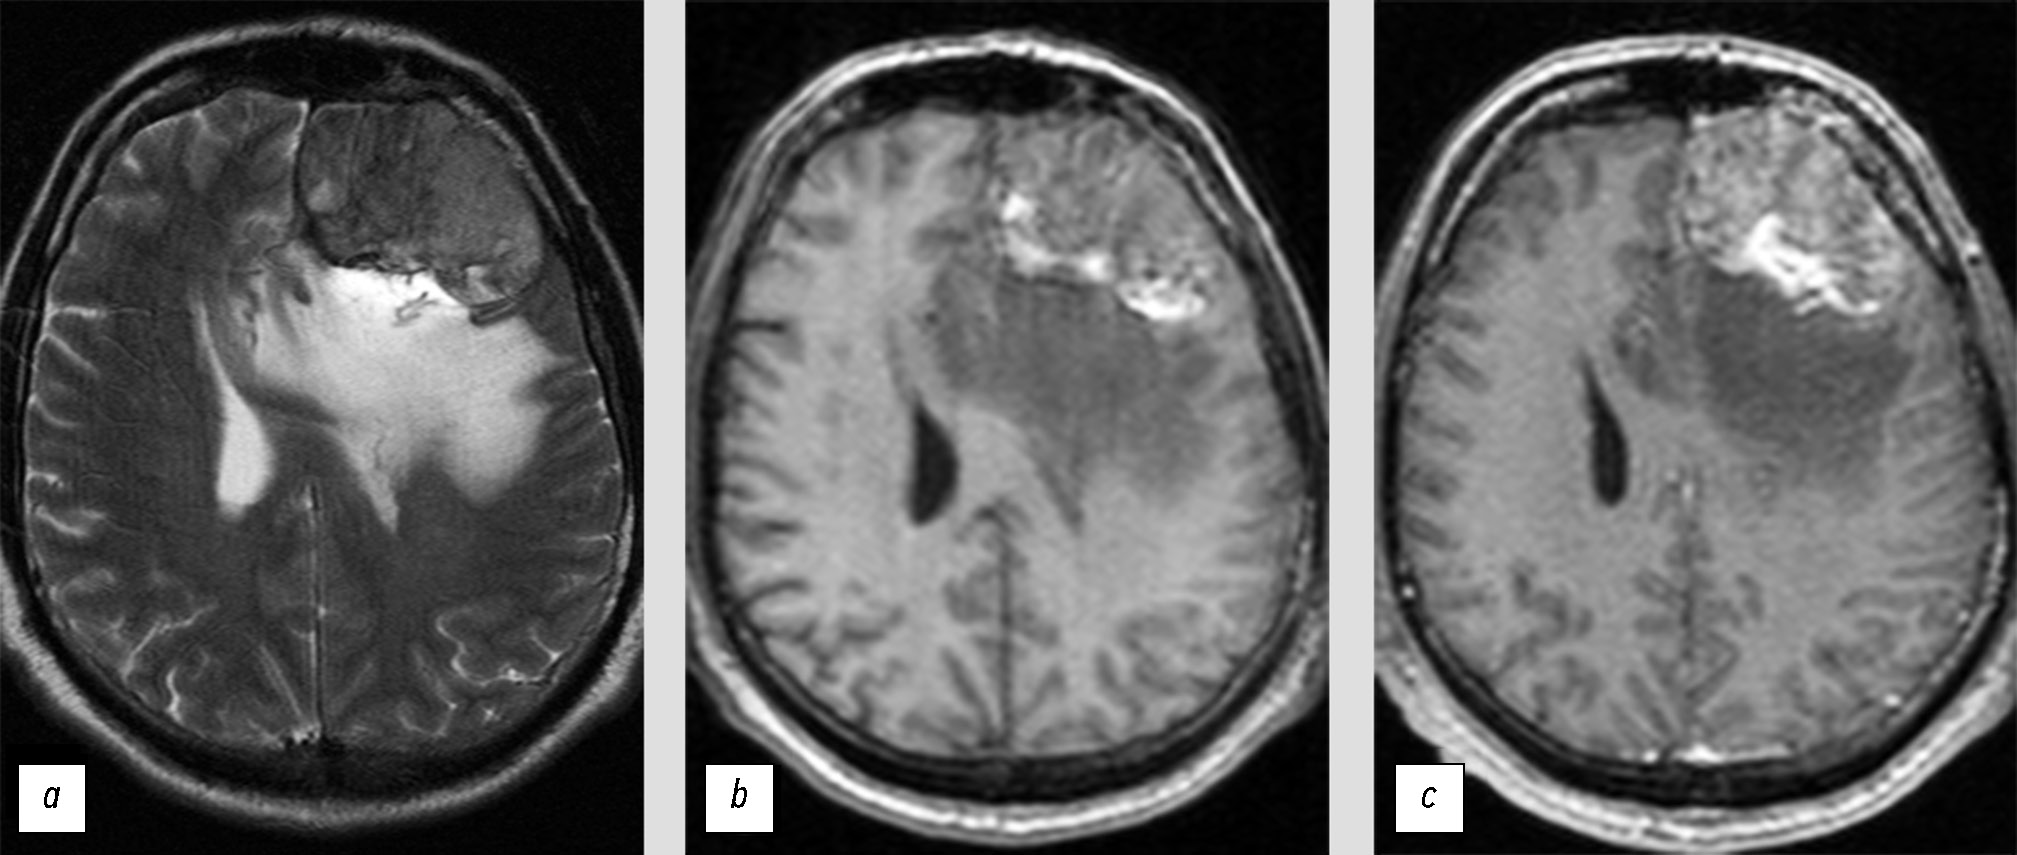

Инструментальная диагностика. При выполнении МРТ-исследования с внутривенным контрастированием (рис. 4) в правой лобной области визуализируется внемозговая опухоль размерами до 4,5×2,0×3,8 см. Структура опухоли однородная, контрастирование гомогенное. По периферии образования определяется зона отёка вещества мозга, контуры образования участками неровные и нечёткие. Отмечается гиперостоз подлежащей кости.

Рис. 4. Отсутствие ликворной щели между доброкачественной менингиомой и веществом мозга, и наличие периферического отёка могут быть интерпретированы как инвазия опухоли: a — Т2-ВИ; b — Т1-CE.

Представлена доброкачественная менингиома (*). Ликворная щель прослеживается только в задних отделах (чёрные стрелки). В передних отделах граница между опухолью и веществом мозга не прослеживается, в данной области определяется периферический отёк (белые стрелки).

Дифференциальная диагностика. Отсутствие чёткого отграничения ткани опухоли от вещества мозга и наличие отёка по периферии послужило основанием ошибочно диагностировать атипичную менингиому. В то же время у данного образования определяются признаки, типичные для менингиом Grade 1: опухоль имеет однородную структуру, отмечается наличие гиперостоза подлежащей кости.

Лечение. Выполнена резекция опухоли, гистологическое заключение: менингиома (Grade 1), С70.0 9530/01.

В двух следующих клинических примерах (рис. 7 и рис. 8) представлены МРТ-изображения пациентов с солитарными фиброзными опухолями. В обоих случаях опухоли на основании оценки МРТ были ошибочно определены как менингиомы. Вероятной причиной диагностических ошибок явилось сочетание двух факторов: редкость СФО и схожесть их МРТ-проявлений с менингиомами.

Рис. 7. Солитарная фиброзная опухоль, имеющая сходную МРТ-семиотику с доброкачественной менингиомой: a — Т2-ВИ; b — Т1-ВИ; c — Т1-CE.

В передних отделах межполушарной щели определяется внемозговое образование (*).

Рис. 8. Солитарная фиброзная опухоль, имеющая сходную семиотику магнитно-резонансной томографии со злокачественной менингиомой: a — Т2-ВИ; b —Т1-ВИ; c — Т1-CE.

Инструментальная диагностика. При выполнении МРТ данных за травматические изменения не выявлено, однако в передних отделах межполушарной щели определяется внемозговое образование, размерами 2,2×1,6×2,3 см (см. рис. 7). Опухоль широко прилежит к серпу большого мозга, чётко отграничена от вещества мозга, структура её достаточно однородная. После контрастирования отмечается невыраженное повышение МР-сигнала от ткани опухоли.

Дифференциальная диагностика. Выявленное образование было ошибочно классифицировано как типичная менингиома. Единственным признаком, позволяющим заподозрить иную опухоль, являлось невыраженное контрастирование, но данный симптом может наблюдаться и при менингиомах.

Лечение. Пациентке выполнена резекция опухоли, гистологическое заключение: гемангиоперицитома/солитарная фиброзная опухоль (Grade 1), С70.0 9150/01.

Инструментальная диагностика. При выполнении МРТ в левой лобной области было выявлено внемозговое образование, размерами до 6,0×4,0×6,3 см (см. рис. 8). Опухоль без чёткого отграничения от вещества мозга, с зоной отёка по периферии. Структура образования неоднородная, в том числе за счёт кровоизлияния. Контрастирование невыраженное и неоднородное.

Дифференциальная диагностика. На основании того, что образование имеет признаки, характерные для злокачественных менингиом, заключение рентгенолога было ошибочным. Выявленное образование отнесено к атипичным менингиомам.

Лечение. Пациенту выполнена резекция опухоли, гистологическое заключение: гемангиоперицитома/солитарная фиброзная опухоль (Grade 2), С70.0 9150/32.